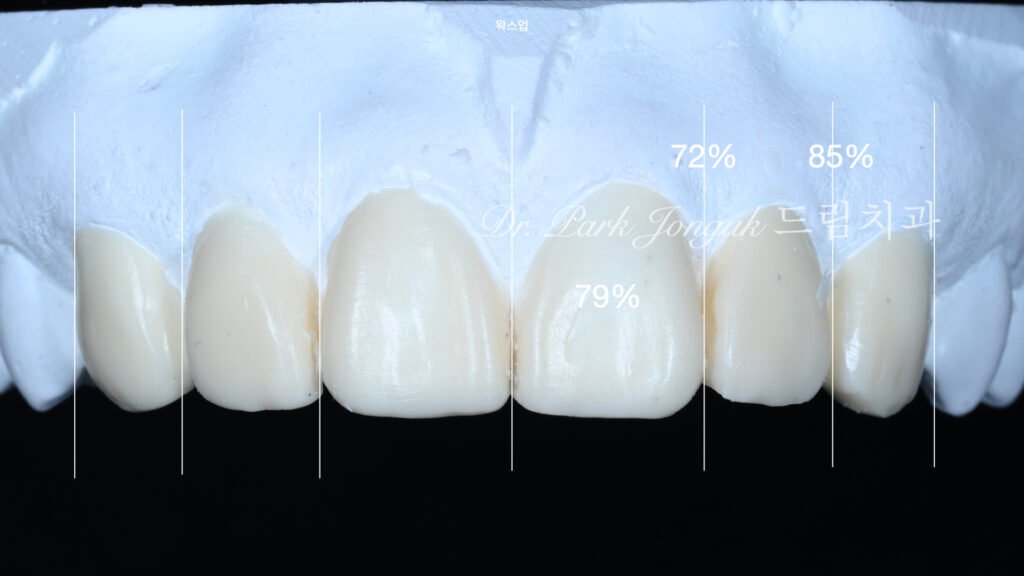

왁스업을 통한 차등 삭제 계획

모든 데이터를 종합하여 진단 왁스업(diagnostic wax-up)을 제작했습니다. 이 과정의 핵심은 각 치아별로 다른 치료 전략을 수립하는 것입니다.

상악 중절치(치아 #11, #21):

- 현재 크기가 상대적으로 크므로 비율 조정 필요

- 계획된 삭제량: 약 0.5+/- 0.3mm (표준 라미네이트 준비)

- 목적: 측절치와의 비율을 1.4:1로 개선

상악 측절치 및 견치(치아 #12, #22, #13, #23):

- 현재 크기가 적정하므로 최소 개입

- 계획된 삭제량: 0-0.3mm (법랑질 표면층만)

- 목적: 변색 제거 및 라미네이트 접착을 위한 최소 공간 확보

이러한 **차등 삭제 전략(differential reduction strategy)**은 불필요한 치아 구조 손실을 방지하면서도 비율 조화를 달성하는 핵심 방법입니다. 전통적 접근법처럼 모든 치아를 균일하게 삭제하면 이미 적정 크기인 치아까지 과도하게 삭제되는 문제가 발생합니다.

크기 및 형태 설계:

- 중절치: 폭은 유지하되 길이를 증가시켜 폭-길이 비율 개선

- 측절치: 폭을 약간 증가시켜 중절치와의 비율을 1.4:1로 조정

- 이를 통한 시각적 효과: 중절치가 상대적으로 작고 날씬하게 보임